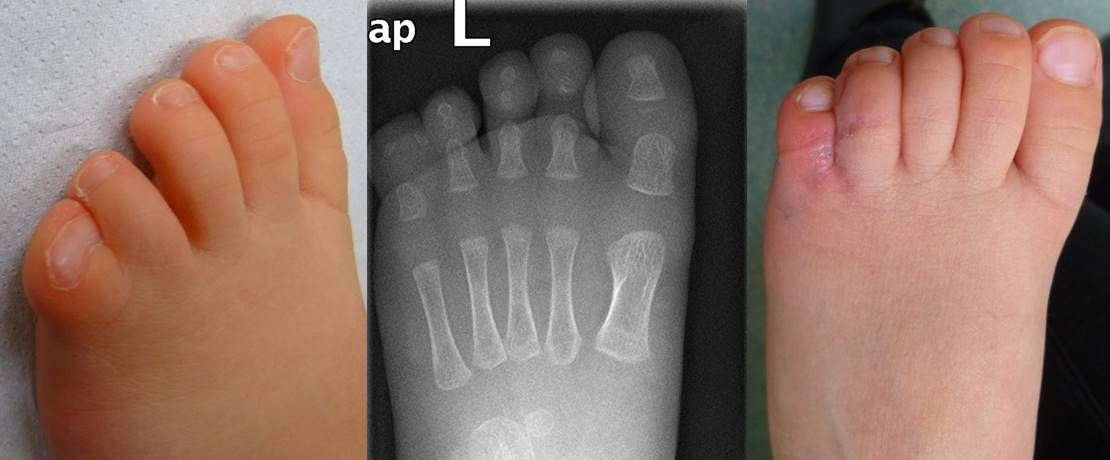

Bei Doppelanlage von Zehen (Hexapododactylie) muss vor allem dann operiert werden, wenn der gedoppelte Anteil deutlich von der Achse abweicht oder der betroffene Fuß deutlich breiter ist als die Gegenseite, weil es sonst Probleme bei der Schuhversorgung gibt. Im Idealfall erfolgt so eine operative Korrektur ebenfalls  kurz nach dem ersten Geburtstag. Manchmal nimmt eine Fehlstellung aber auch erst im Laufe des Lebens deutlich zu und kann dann mit etwas mehr operativem Aufwand auch beim Jugendlichen noch gut korrigiert werden.